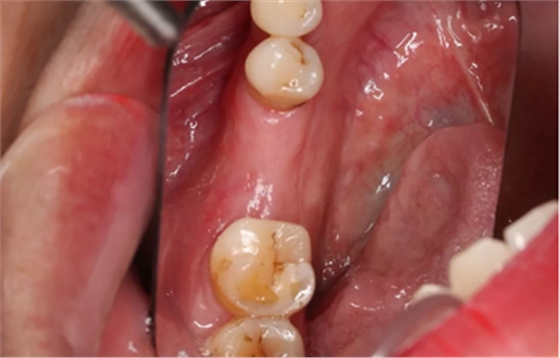

2、术前口腔内照片

46牙烤瓷冠修复,牙周红肿,叩痛,松2度。骨吸收波及邻牙,邻牙牙周情况不佳,45牙松2度,47牙松1度。

(摄于2016年8月31日,反光板协助拍摄)